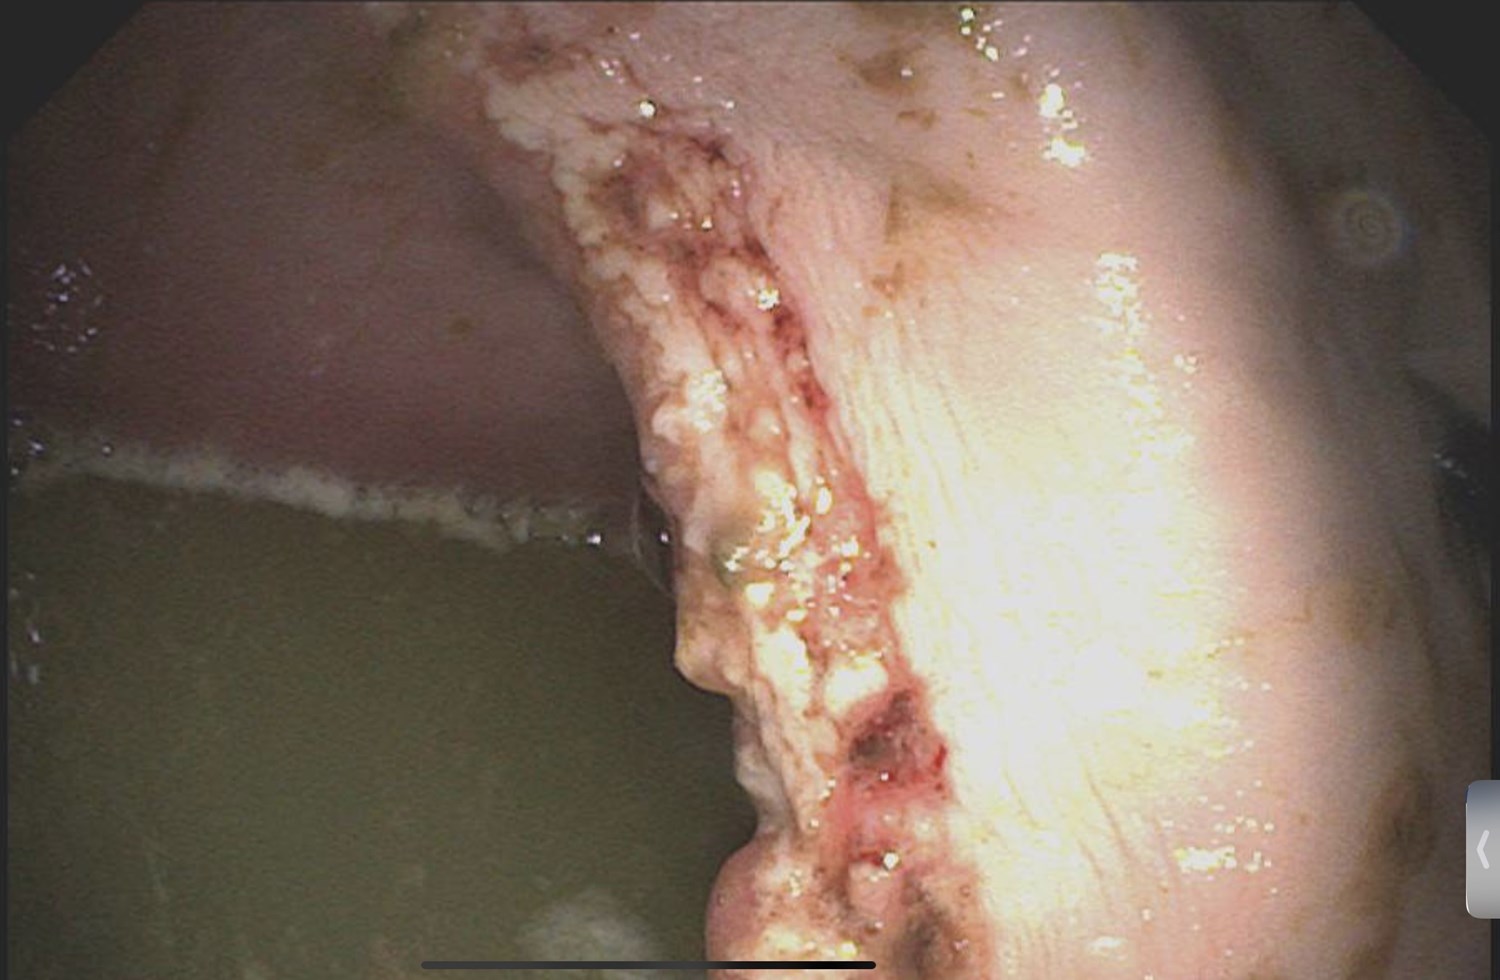

Hvad er hyppigste problemer og symptomer ved manglende hestetandpleje? I slemme tilfælde kan hesten have tandkødslommer der bevirker at især grovfoder kommer ud i klumper. Dette er en meget ubehagelig lidelse for hesten, der i slemme tilfælde kan forhindre den i at optage grovfoder overhovedet.

• Sår i mundvige eller kinder